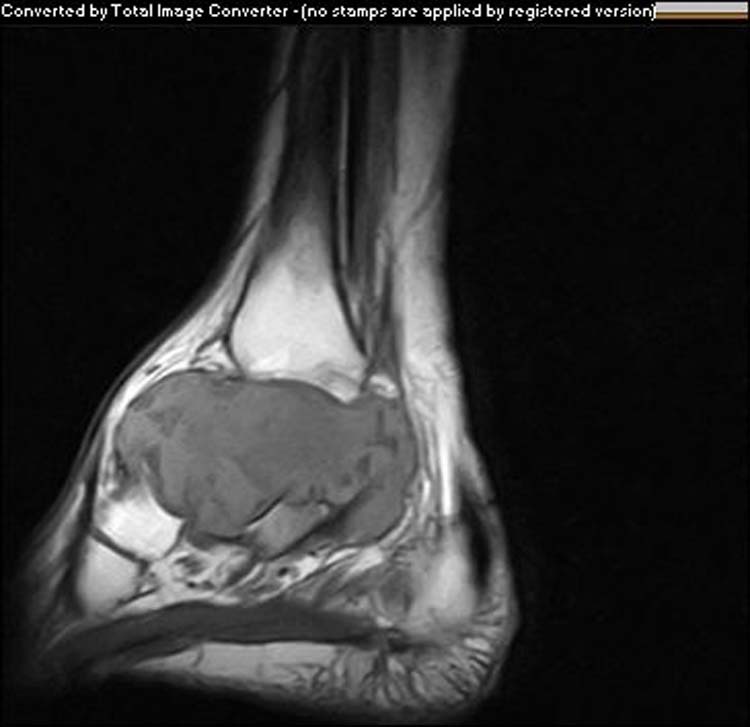

From www.researchgate.net

The MRI shows pedicled bone tumor arising from the talus. Download Talus Bone Tumor Osseous neoplasms of the foot are uncommon, accounting for only 3.3% of all primary bone tumors. Radiologists as well as orthopaedic surgeons need to be aware of such. Radiologists as well as orthopaedic surgeons need to be. Results revealed 75 cases of talar lesions. Osseous neoplasms of the foot are uncommon, accounting for only 3.3% of all primary bone tumors.. Talus Bone Tumor.